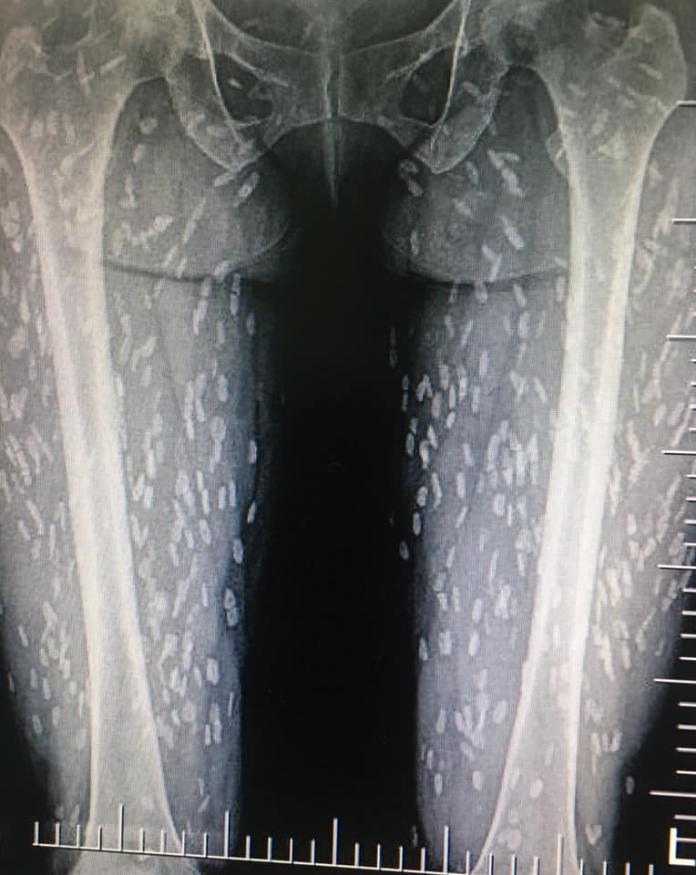

泰國Kwang Volemage網友在臉書分享一名女病患的X光照片,只見有大量一段一段的白色斑點遍布在患者的雙腿。據網友指出,這名女患者吃了生豬肉後,開始出現呼吸困難等症狀。經緊急檢查後才發現,原來身體已經被大量的豬肉絛蟲與幼體豬肉囊蟲寄生。

▲女子腿部已經被大量寄生蟲佔據。(圖/翻攝自Kwang Volemage臉書)

據了解,豬肉絛蟲是人畜共通寄生蟲,人類常是最終宿主,豬絛蟲進入人體後產卵,孵化的幼蟲會穿過腸壁進入腹腔後亂跑,常寄生在橫紋肌。不過通常只要煮熟豬肉,寄生蟲就會被高溫殺死。